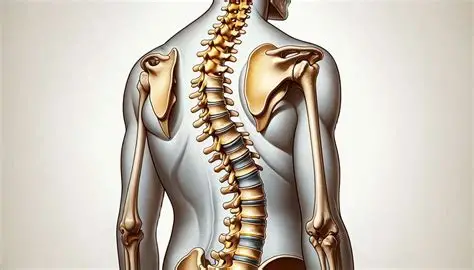

Çfarë është skolioza?

Skolioza është një devijim anësor i shtyllës kurrizore, i shoqëruar shpesh me rrotullim të vertebrave. Kjo gjendje mund të shfaqet në fëmijëri, adoleshencë, por edhe tek të rriturit si pasojë e qëndrimit të gabuar apo problemeve muskulore.

Simptomat

Disa nga shenjat më të zakonshme përfshijnë:

- shpatulla të pabarabarta

- një anë e trupit më e ngritur

- devijim i shtyllës kurrizore

- dhimbje në shpinë dhe qafë

- lodhje gjatë qëndrimit në këmbë